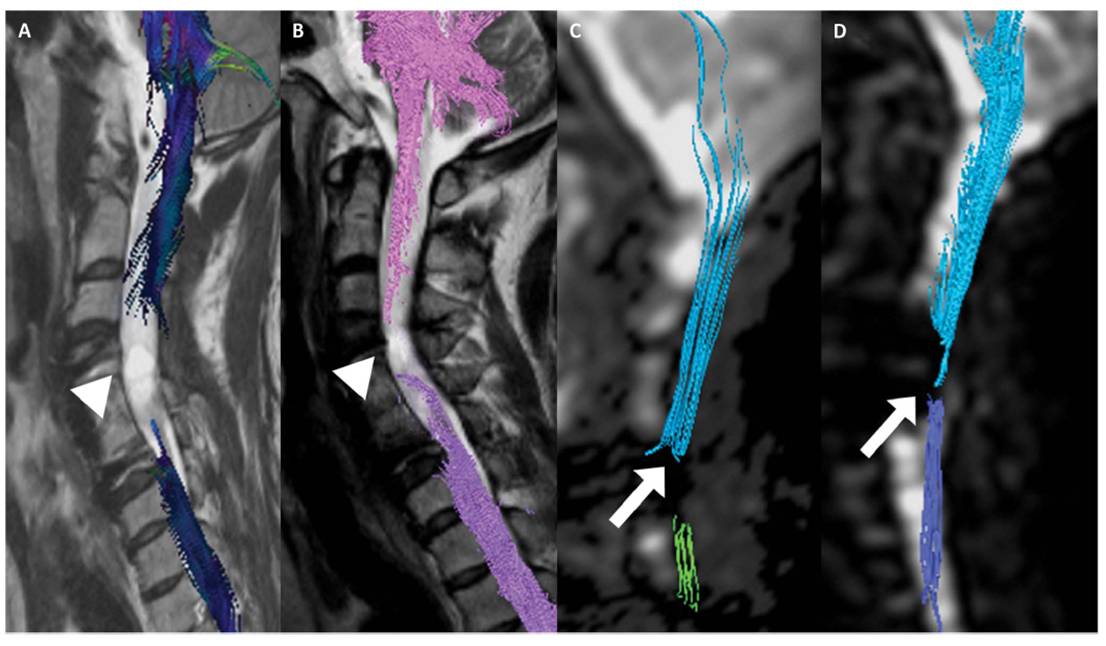

이어 “그러나 줄기세포치료제를 단회 투여했음에도 불구하고 호전된 환자의 척수 MRI 및 DTI 검사 결과 척수손상 부위에서 줄기세포치료 전에는 없던 섬유의 연속성(fibercontinunity)이 확인되는데 이는 줄기세포치료로 인한 신경재생 효과로 판단할 수 있다"고 말했다.

[환자의 DTI검사결과다. 줄기세포치료제 투여하기 전(A와C)에 비해 투여 후 6개월이경과한 후(B와 D)에는 끊어진 척수신경이 재생되었음을 확인할수 있다